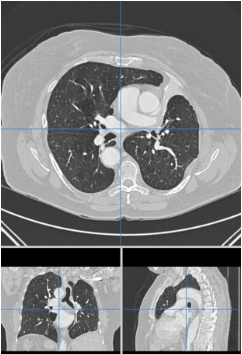

3 数据集描述与CT图像简介

计算机断层扫描(Computer Tomography, CT)成像系统通过X射线束与高灵敏度探测器协同作用,在人体某一特定部位进行扫描而形成二维断层影像。 chest CT成像系统生成一系列连续的横断面图像切片, 其中包含从数十到数百张不等的高分辨率横断面. 如果将所有切片叠加后构建起完整的3D人体胸腔模型, 如下图所示:

在进行 lung CT image slicing时,在图像中间较暗的区域属于人体胸腔的主要器官之一——即所谓的" lung parenchyma"部分;而位于较高亮度区域的组织包括血管和空气等器官系统。 lung nodules通常会聚集在其对应的 parenchyma 区域内。如图所示,在该切片中可见一个含有的 lung nodule标本: